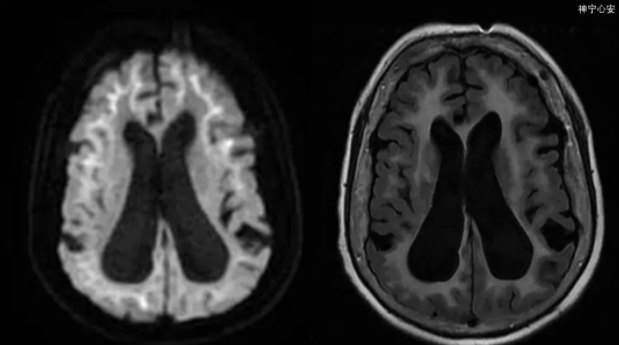

不到60岁却“老态龙钟”? 记忆力下降、反应迟缓、步态异常……警惕这种疾病不“动”的信号!

我国中老年人继心脑血管、癌症之后的“第三杀手” —— 帕金森病,你了解多少?